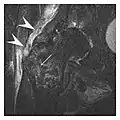

The greater tuberosity of the humerus is also an illustrative location of occult fractures. The osseous injury may follow seizures, glenohumeral dislocation, forced abduction, or direct impaction. They are commonly discovered on MRI in symptomatic patients with suspicion of rotator cuff tear. Coronal images are best suited for detection. They appear as crescentic oblique lines surrounded by a bone marrow edema pattern (Figure 5). The rotator cuff must be inspected since associated ligamentous lesions are common. In the ankle, malleoli and tarsal bones should be checked carefully for any cortical disruptions and radiolucent lines that may reveal a fracture. Awareness of the exact location of the pain will help direct the attention of the interpreter when searching for very subtle signs of fracture (Figure 6).[1]

a

b

Figure 6: Subtle anterior talar fracture in a 39-year-old man presenting with ankle pain after a fall. (a) Anteroposterior radiograph shows a subtle oblique radiolucent line through the talus (white arrows). (b) Sagittal CT reformation confirms the presence of an anterior talar fracture with cortical offset (black arrow). Avulsion fractures, which consist of a detached bone fragment resulting from a ligament or tendon pulling away from the bone, may also present with subtle radiographic signs. Tiny osseous fragments near the presumed attachment site of a ligament suggest this diagnosis. Common sites are the lateral tibial plateau (the Segond fracture), the spinal tuberosity of the tibia resulting from anterior cruciate ligament avulsion, and the ischial tuberosity.[1]